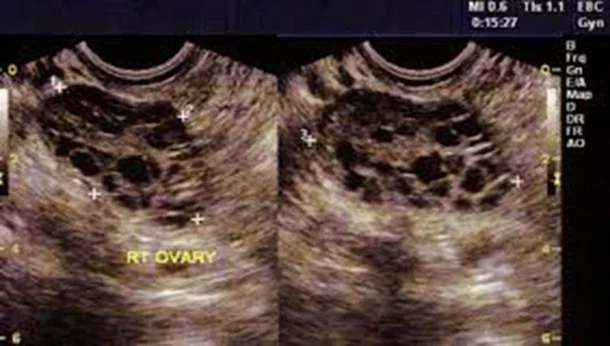

- The ultrasound criteria for the diagnosis of a polycystic ovary are:

- Eight or more subcapsular follicular cysts <10 mm in diameter.

- Increased ovarian stroma.